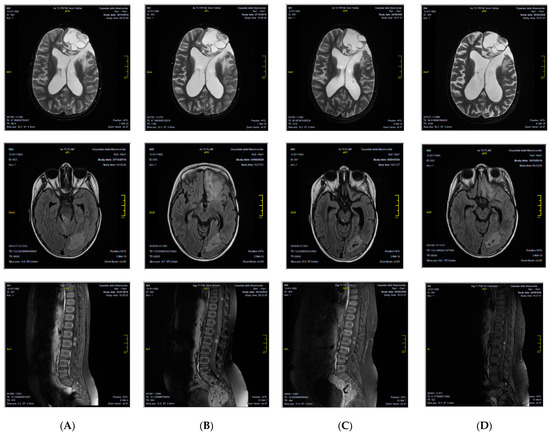

A 7-year-old female patient from Morocco came to our attention with a diagnosis of relapsed grade III EPN 4 years from the primary diagnosis, which was made in her origin country, done after seizure appearance. The tumor was localized in the left frontal lobe and was completely removed by surgery. From December 2016 to February 2017, the child received three courses of adjuvant chemotherapy with cisplatin and etoposide. In March 2017, a relapse occurred in the primary tumor site. It was treated with surgery and three courses of chemotherapy with ifosfamide and etoposide. Complete remission was obtained. In October 2017, a second relapse occurred again in the left frontal lobe, which was treated with surgery and radiotherapy (59.4 Gy). Complete remission was achieved. In April 2019, a third relapse was diagnosed, and the patient was considered incurable in her origin country. For this reason, she was referred to our Center, where a full CNS magnetic resonance imaging (MRI) evaluation documented a multifocal disease both in the brain and in the spinal cord. CNS fluid analysis was negative for leptomeningeal dissemination. We decided to treat her with oral etoposide and dexamethasone. A follow-up MRI done in October 2019 showed a disease progression, but clinical conditions were still good, and we did not modify the current treatment. In December 2019, the patient was admitted to the hospital due to worsening general clinical conditions, which moved rapidly to a comatose state. We administered anti-edema treatment with high-dose dexamethasone and 20% mannitol, with an improvement of the clinical feature. The MRI showed an ulterior disease progression. For this reason, we decided to substitute etoposide with temozolomide. In January 2020, the patient was again admitted to the hospital because of neurological symptoms (headache, vomiting, and hyposthenia of the right part of the body); anti-edema treatment was done and then radiotherapy on the left frontal lesion. We obtained histological material from the last surgery done in her origin country. Diagnoses of anaplastic ependymoma with RELA gene expression were confirmed. The immune phenotype analyses on paraffine tumor sample revealed: p65+, LICAM+, OLIG2-, p53+, GFAP+, EMA+, Synaptophysine+, ATRX+, m-TOR+, PD-L1+ (20%), and PD-1-. Based on these findings, in February 2020, we decided to start targeted therapy with orally dispensed sirolimus 2 mg/Kg/day every day and IV nivolumab 3 mg/Kg every 2 weeks. Sirolimus dosage was modulated on patient plasmatic concentration. Local Ethics Committee approved the nivolumab off-label use, and written informed consent was signed by the parents, according to the Declaration of Helsinki. Treatment was continued for 1 year until disease progression. During this period, the patient experienced a varicella-zoster virus (VZV) infection, which required IV acyclovir, and dexamethasone was definitively withdrawn (July 2020). In April and August of 2020, control MRI showed substantially stable disease in both the brain and the spinal cord (Figure 1). At one-year follow-up, the patient had disease progression; however, her current clinical conditions are good and neurological assessment completely negative.

Figure 1. CNS MRI patient evaluation during therapy with nivolumab and sirolimus, showing a substantially stable disease in the brain and in the spinal cord at different time points. (A) January 2020; (B) April 2020; (C) August 2020; (D) January 2021.